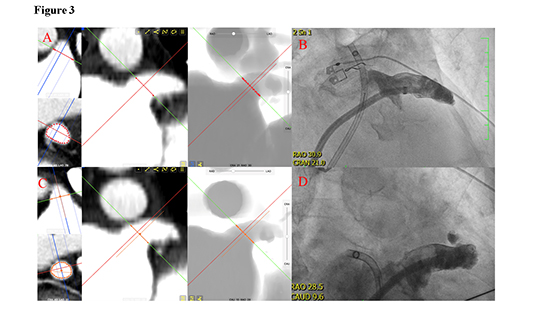

Figure 3. Example of the fluoroscopic projection angles of a patient with a typically located LAA

In a patient with a typically (superiorly-anteriorly) located LAA, the optimal fluoroscopic projection angles (as assessed using cCT analysis) well corresponded with the generally recommended fluoroscopic projection in RAO 30° - CRA or CAUD 10-20°)